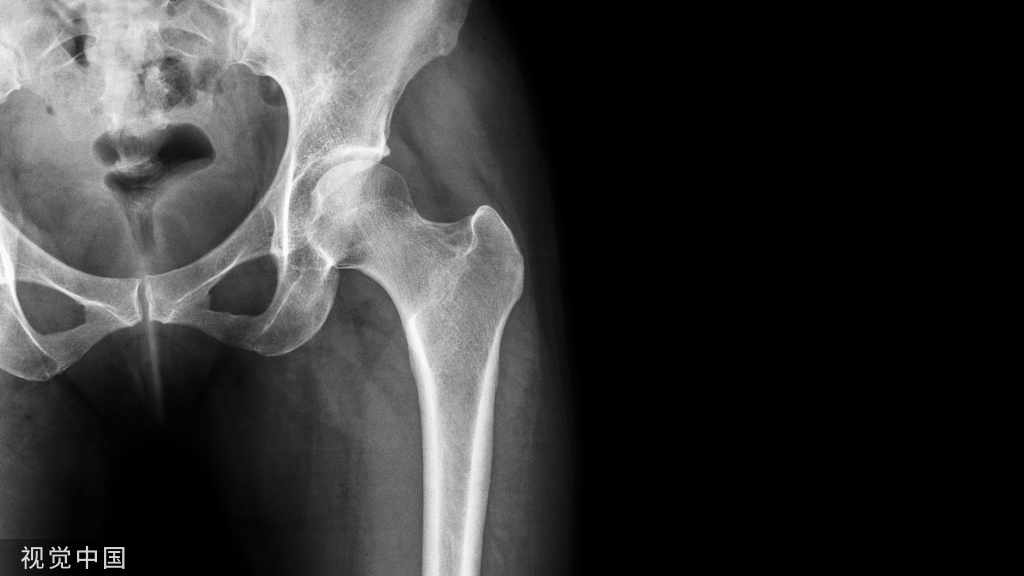

近年来,髋、膝骨关节炎、髋部骨折等疾病发病率呈逐步上升趋势。全髋、膝关节置换术(THA/TKA)是治疗终末期髋、膝关节疾病与老年髋部骨折有效的治疗手段;手术量也逐年增长。尽管人工关节置换技术目前较成熟,但手术出血量大,围手术期贫血及异体输血率高的问题仍较为严重。